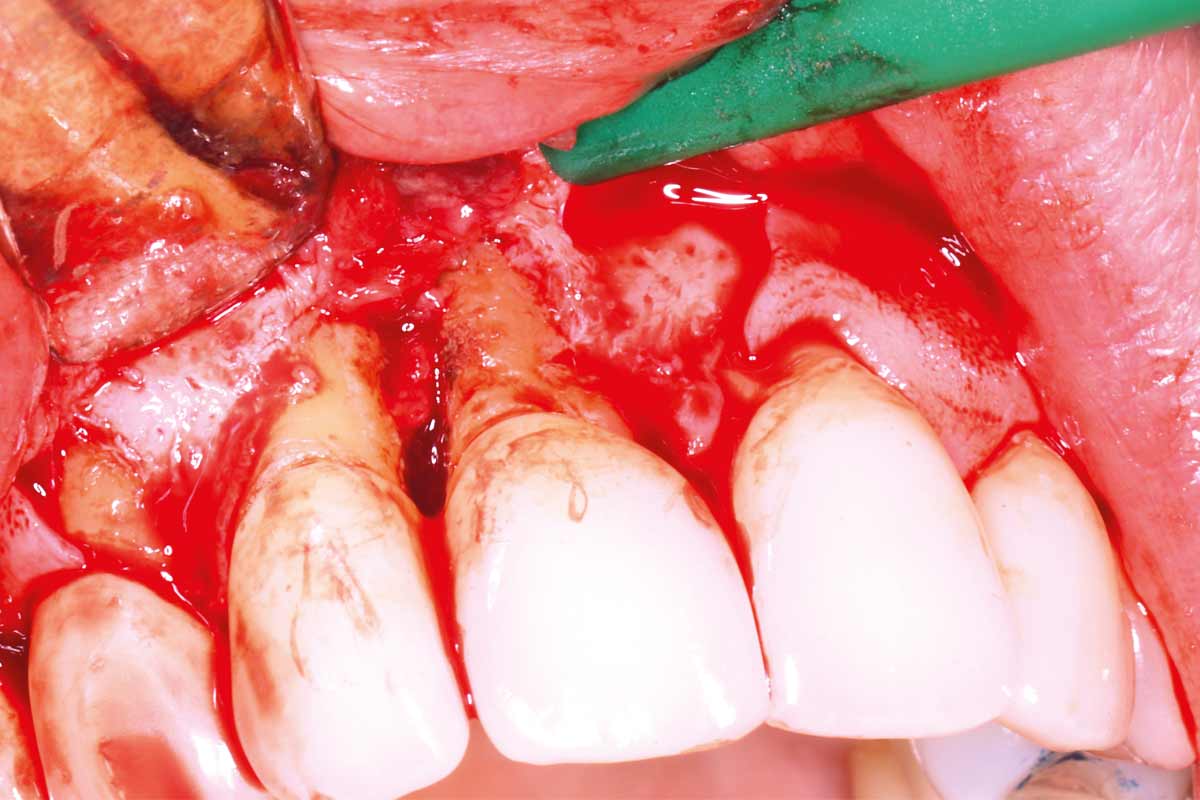

02/10 - Intra-sulcular incisions with 15c blade, vertical releasing incisions realized on the mesial aspect of 13 and 11Maxillary bone reconstruction in the anterior area with cerabone® and Jason® membrane - Dr. P.-Y. Gegout & Prof. O. Huck